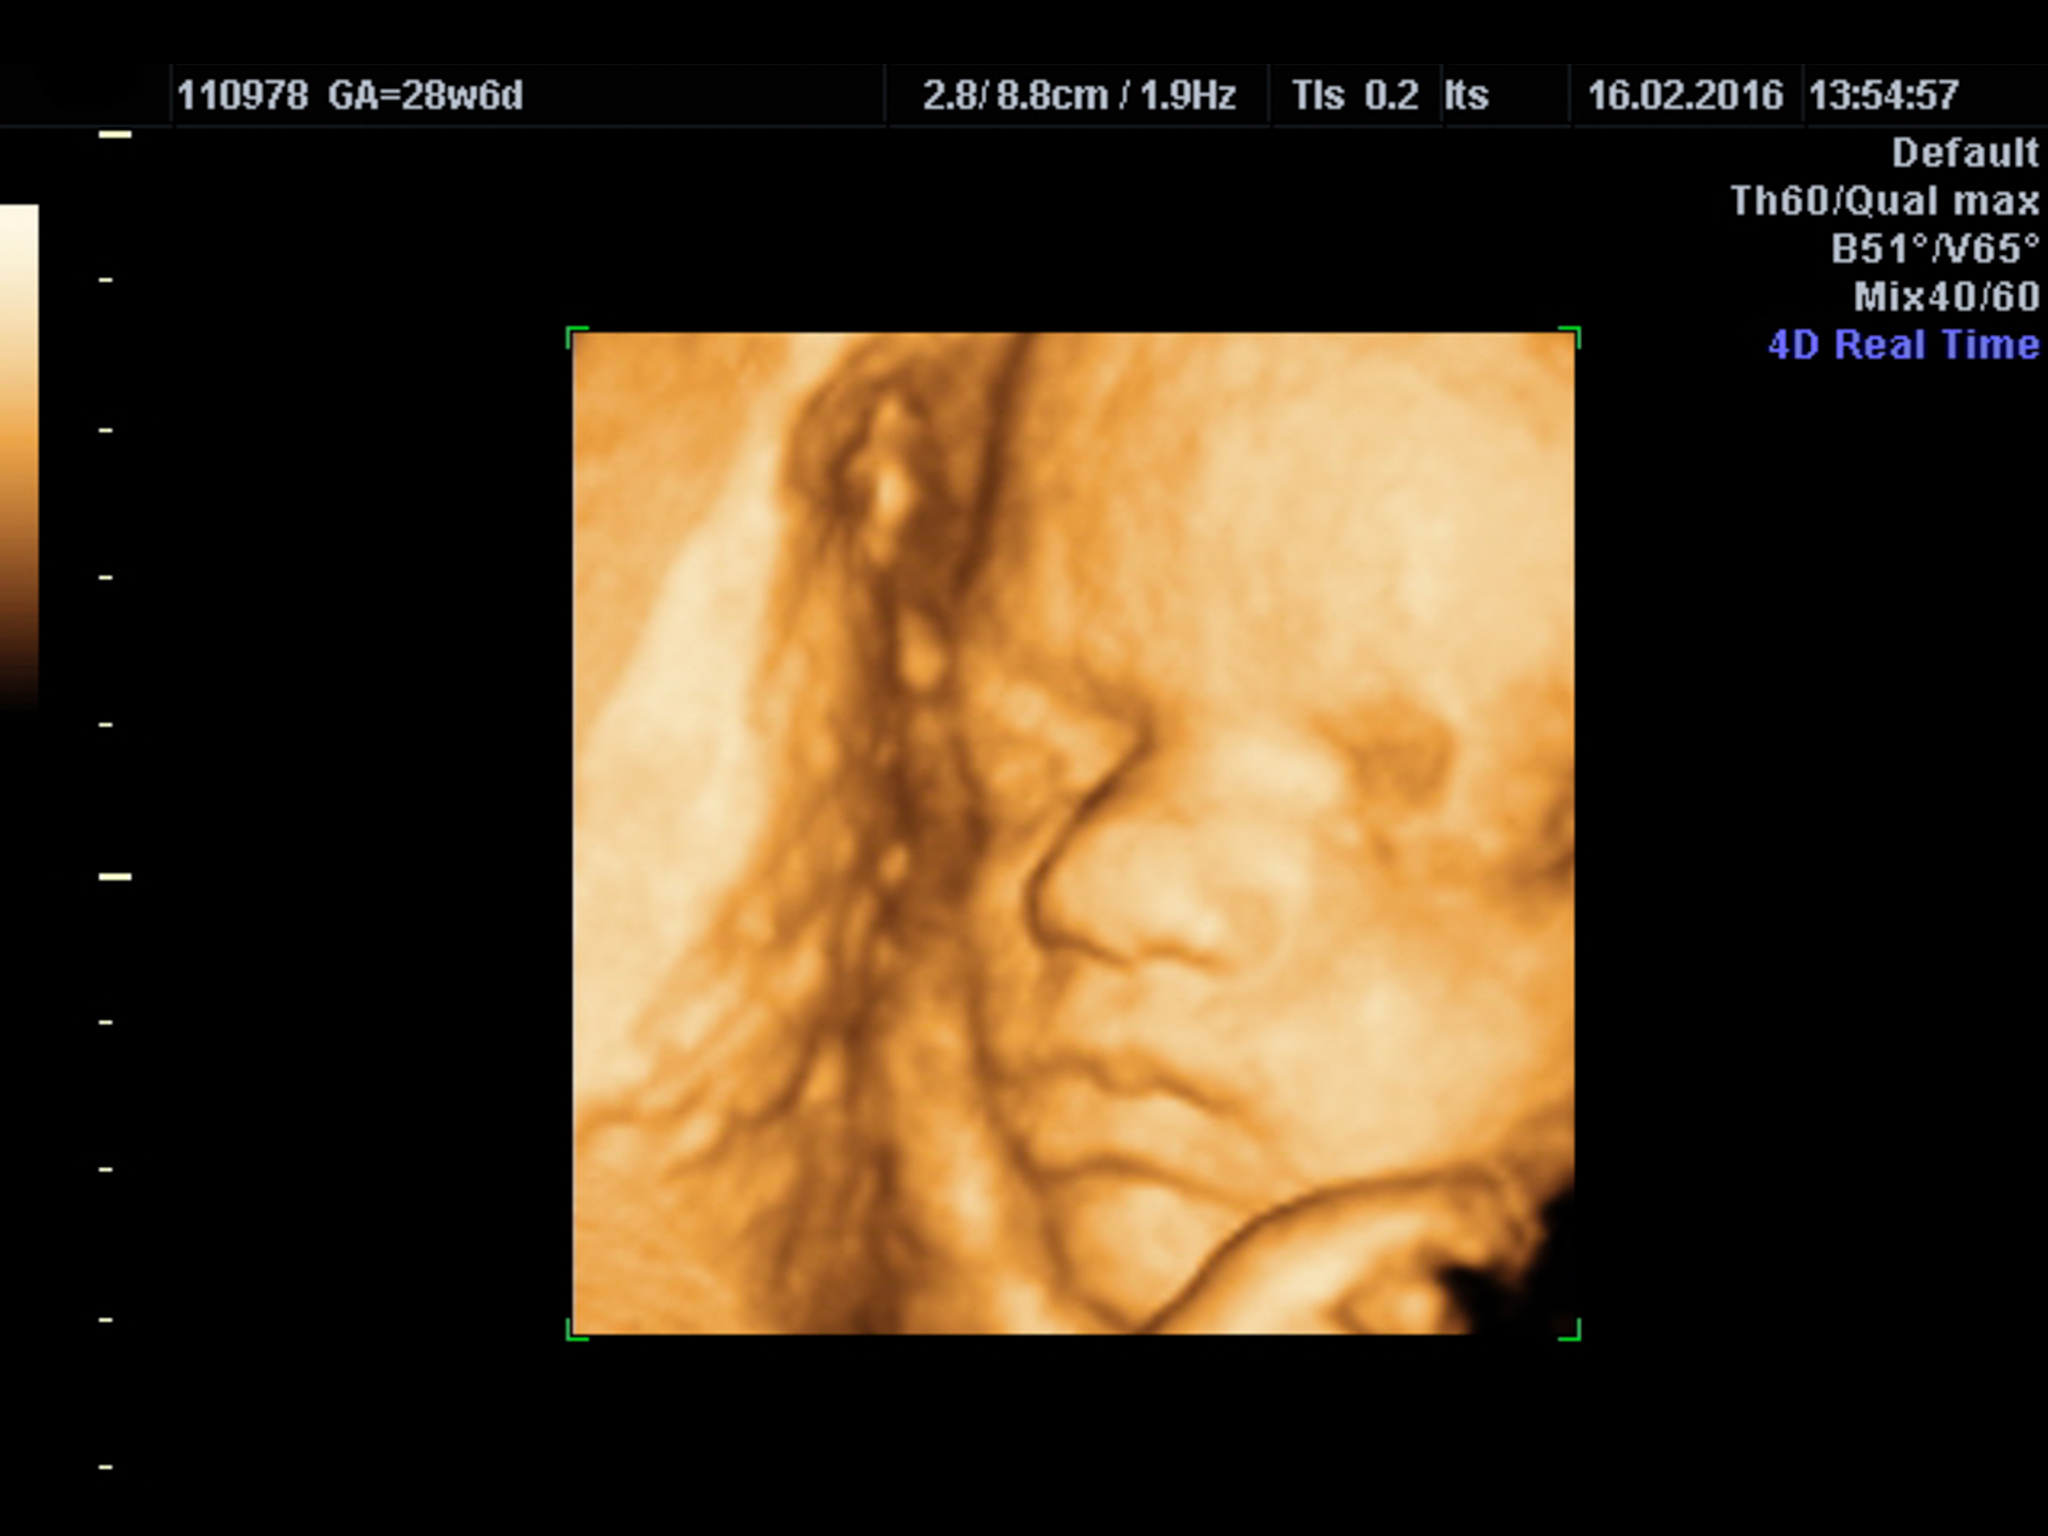

四维羊水最大深度80.7mm表示胎儿周围羊水的最大深度为80.7毫米。羊水是胎儿在子宫内生长发育过程中所处的环境,它提供了对胎儿的保护和支持。四维超声检查是一种通过多个角度观察胎儿的实时三维图像的技术,可以提供更详细和准确的胎儿生长和发育信息。80.7mm的羊水深度在正常范围内,这意味着胎儿的羊水环境良好。